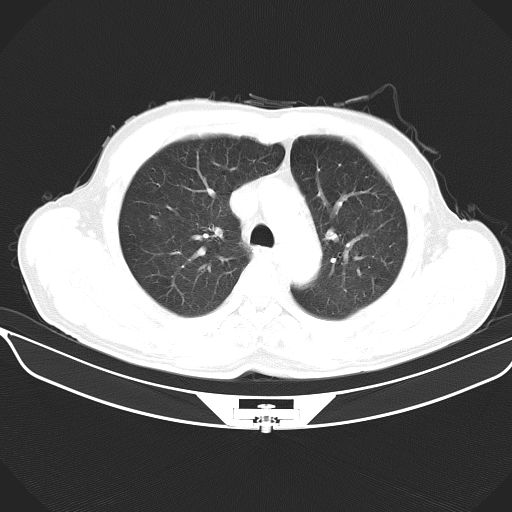

以下是引用心路寻觅在2010-3-1 10:23:00的发言:[br]1、考虑左肺上叶周围型肺癌[br]2、右上肺陈旧性病灶。[br][br][本贴已被 心路寻觅 于 2010-3-1 10:40:18 修改过]

以下是引用shuiyuan在2010-3-1 10:45:00的发言:[br]考虑左肺上叶中心型肺癌伴阻塞型炎症,邻近胸膜受侵。